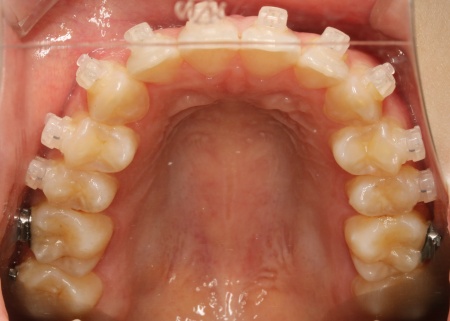

20代女性 乱れた上下の歯並びをハイブリッド矯正で改善した症例

拝見したところ、上下の歯はデコボコに生えている状態でした。

まずは歯の表面にセラミックブラケットを装着し、ワイヤー矯正で歯を全体的に移動させます。